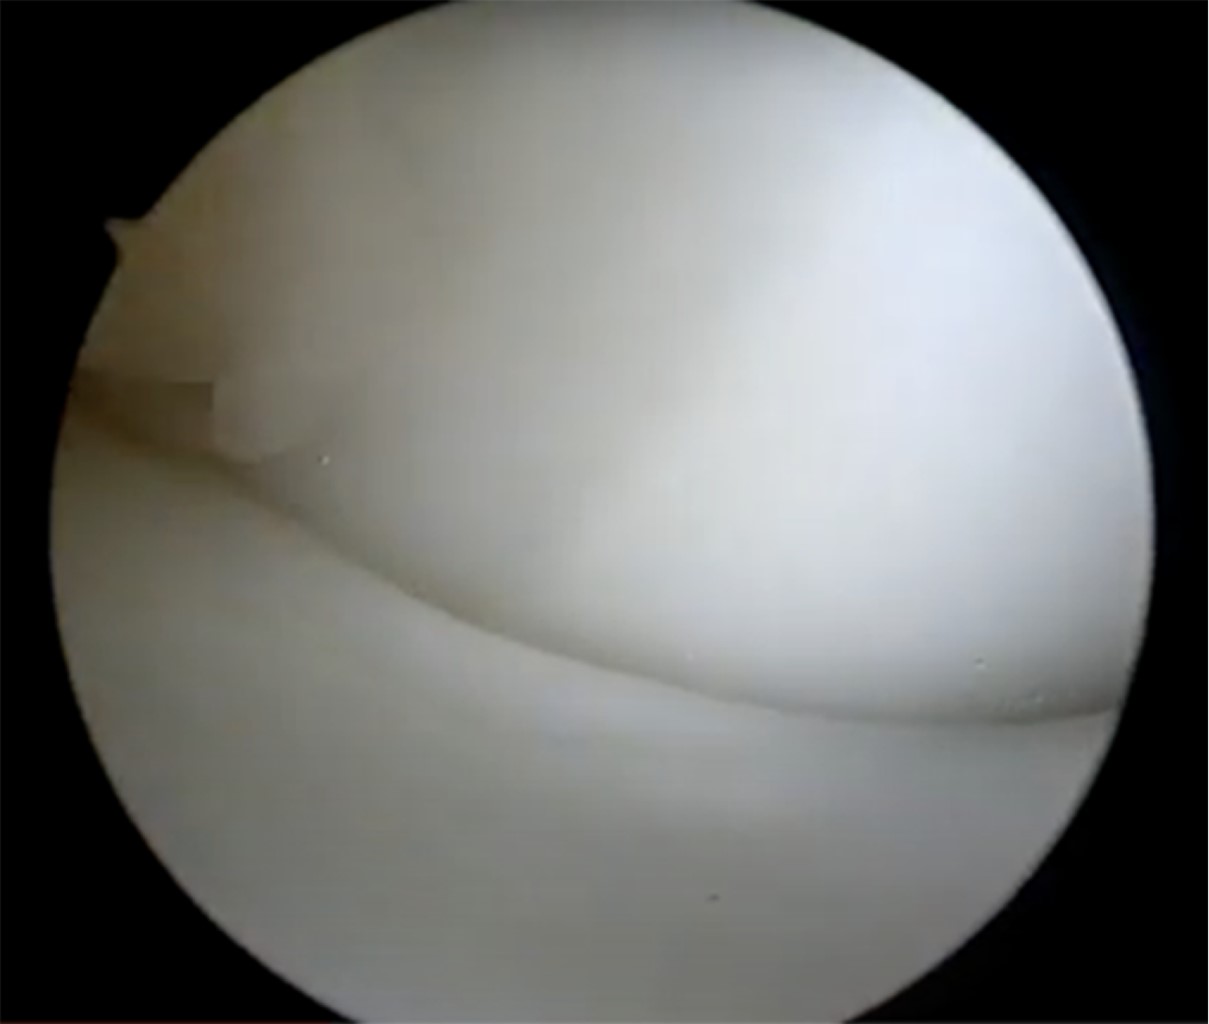

Durante la artroscopía de la rodilla derecha, se encontró una lesión compleja en el menisco medial, que fue diagnosticada como un menisco discoide. Además, se observó una abundante sinovitis y Hoffitis, así como la presencia de una banda fibrosa en la parte ventromedial (Figuras 3 y 4). Se realizó una plastía del menisco medial mediante saucerización y se determinó que el menisco medial estaba estable, por lo que no se requirió el uso de suturas meniscales (Figuras 5, 6 y 7). También se realizó la resección de la banda fibrosa, sinovectomía y Hoffectomía.

Figura 3

Figura 4